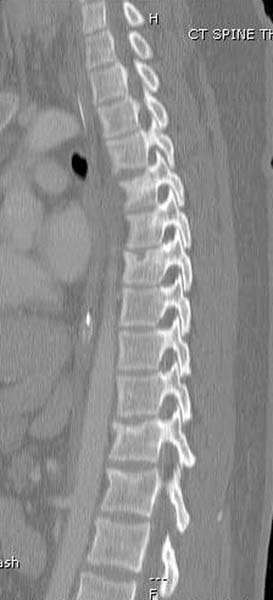

2. Про хребет бы тоже чего- написаь-то

Перелом позвоночника и боковую компрессию таза отнесли к стабильным переломам и не стали форсировать события до лучших времен...

После спадения отека на стопе произведена фиксация тарана. Кстати, коллеги пересмотрели первоначальную консультацию по позвоночнику и на двух уровнях провели фиксацию. Из-за длительного постельного режима без нагрузки таз не стали оперировать...